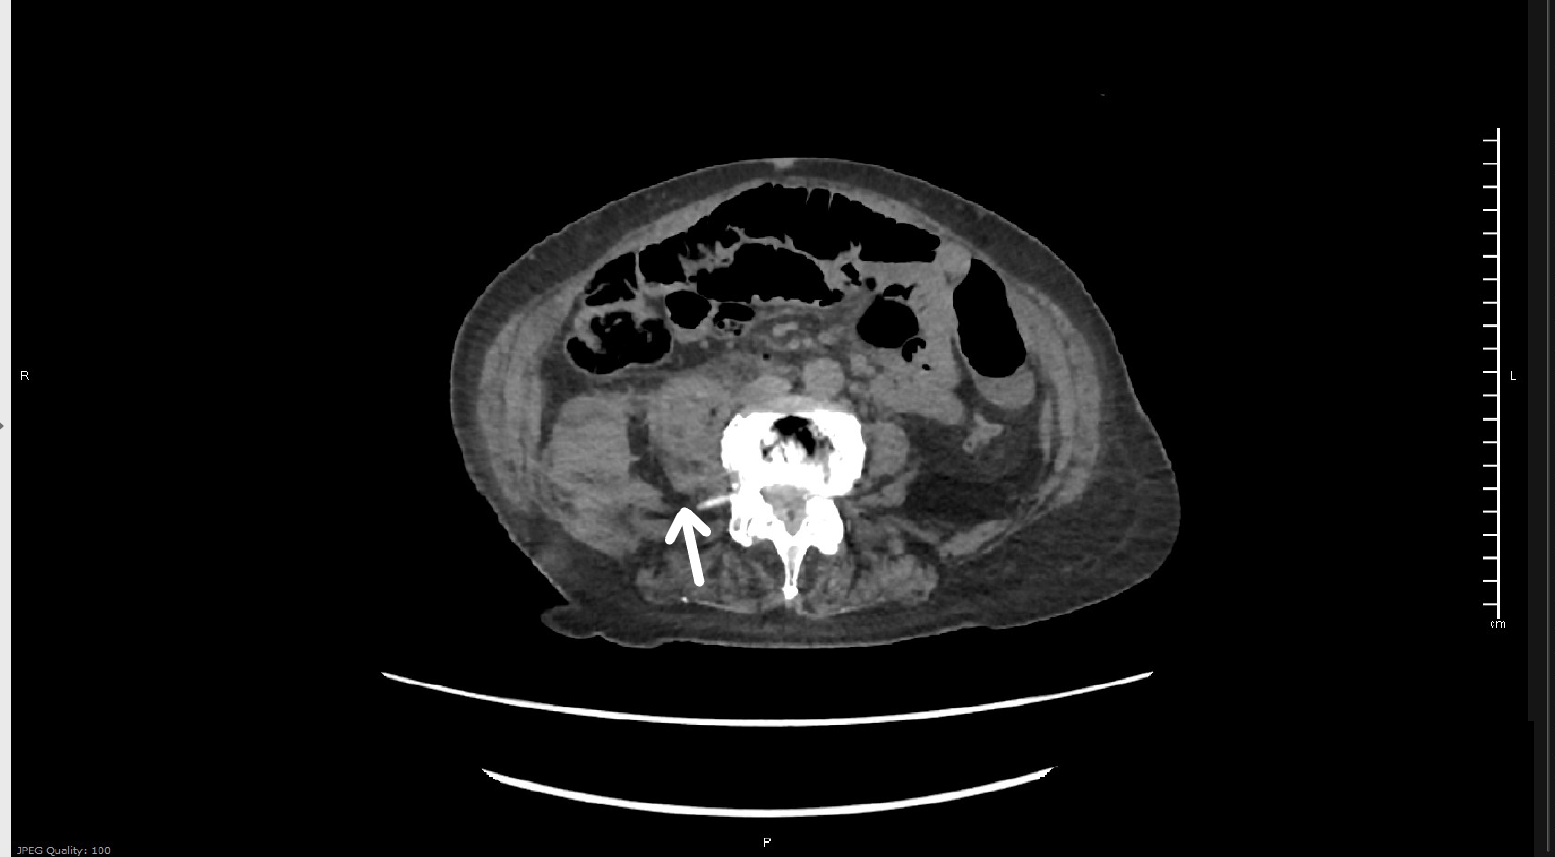

Investigate the pressure of this tangled case of a patient with a limb-threatening injury at first discharged home in the absence of a fracture.